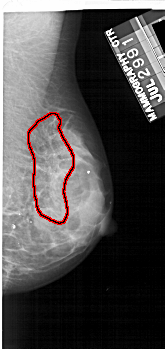

A_1734_1.LEFT_MLO

LEFT_MLO LINES 5176 PIXELS_PER_LINE 2326 BITS_PER_PIXEL 12 RESOLUTION 43.5 NON_OVERLAY

FILE: A_1734_1.RIGHT_MLO.OVERLAY

TOTAL_ABNORMALITIES 1

ABNORMALITY 1

LESION_TYPE CALCIFICATION TYPE PLEOMORPHIC DISTRIBUTION SEGMENTAL

ASSESSMENT 4

SUBTLETY 3

PATHOLOGY BENIGN

TOTAL_OUTLINES 1

BOUNDARY